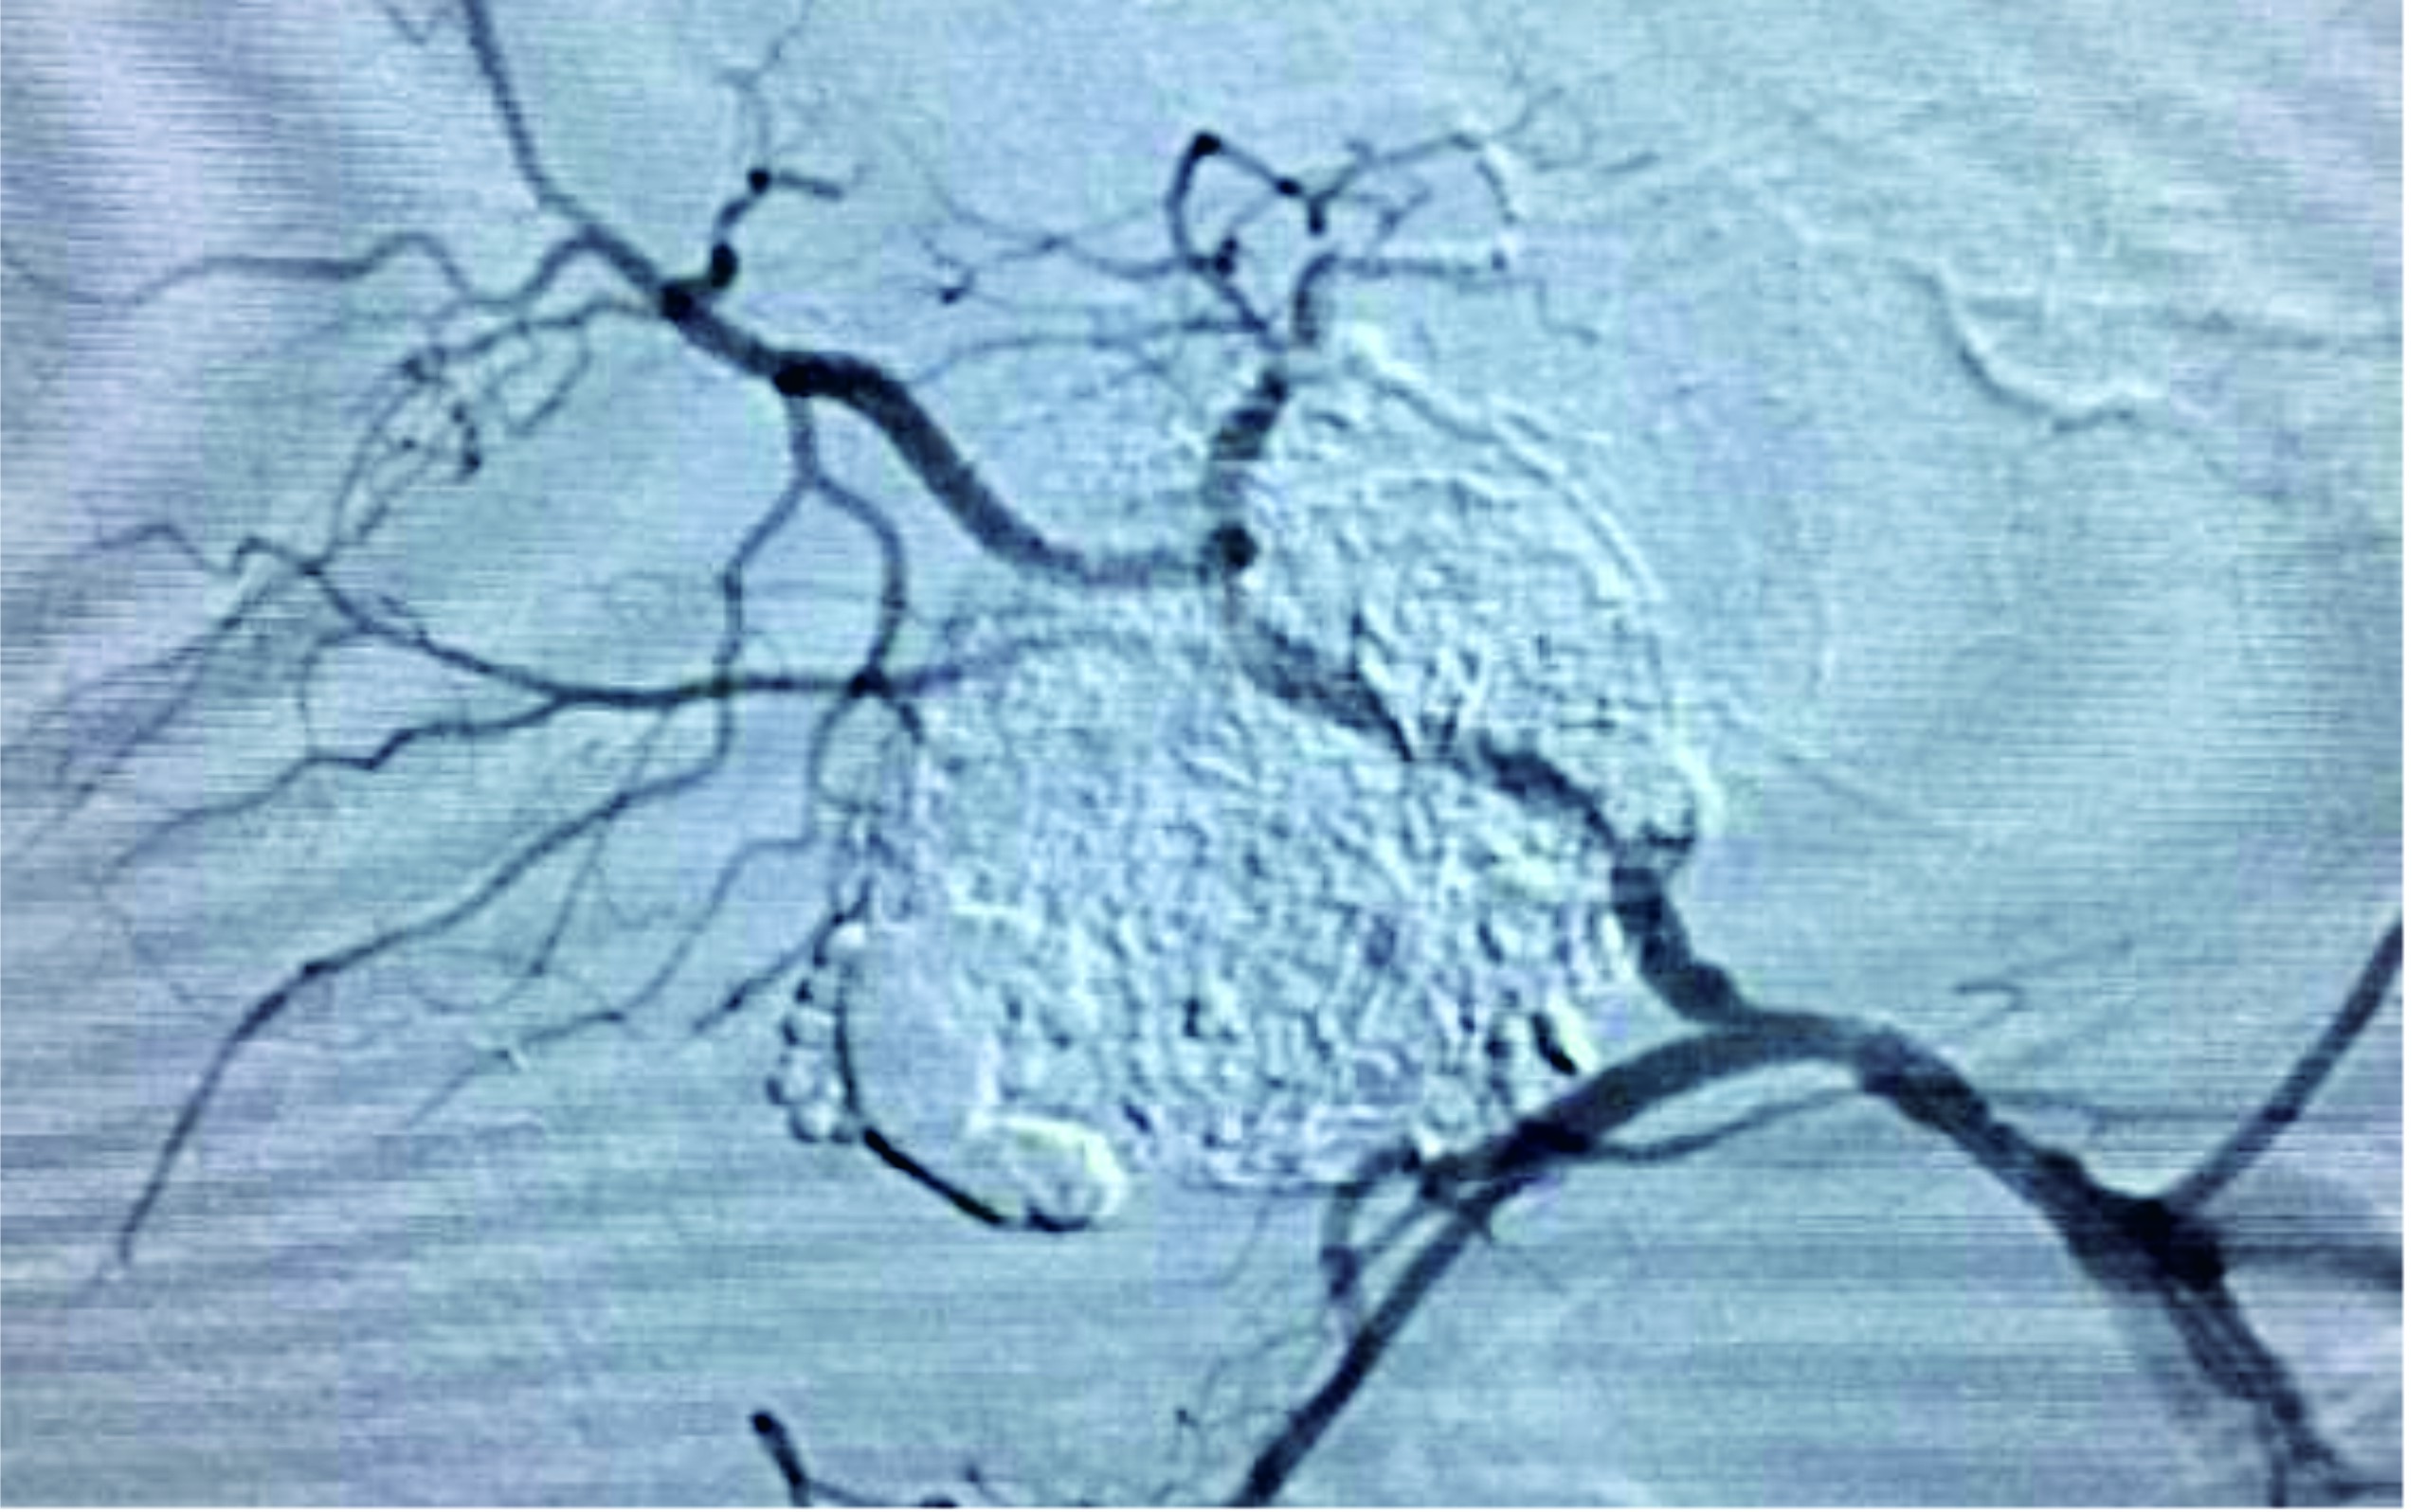

介入治疗,是一种在医学影像设备(如DSA、CT、超声)的引导下,通过一根细细的导管或其他微小器械,经人体自然腔道或微小的穿刺口,直接到达肿瘤部位地行精准打击的现代高科技治疗方法。包括TACE(经动脉化疗栓塞术)-最经典、应用最广;HAIC(肝动脉灌注化疗);局部消融治疗(如微波、射频消融等)。

2、精准直达,药到病除:将高浓度化疗药物和栓塞剂直接注入肿瘤供血血管,实现“局部高浓度化疗”,大幅降低全身副作用;

3、阻断粮草,“饿死”肿瘤:栓塞肿瘤的供血动脉,切断氧气和营养供应,导致肿瘤细胞缺血坏死;